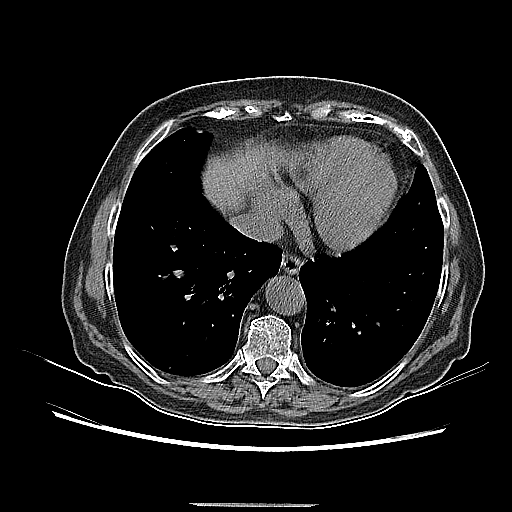

Original NATIVE CT scan (input)

Full window (WL 1023.5, WW 4095 β†’ Low βˆ’1024, High +3071)

Reconstructed NATIVE CT scan (cycle consistency)